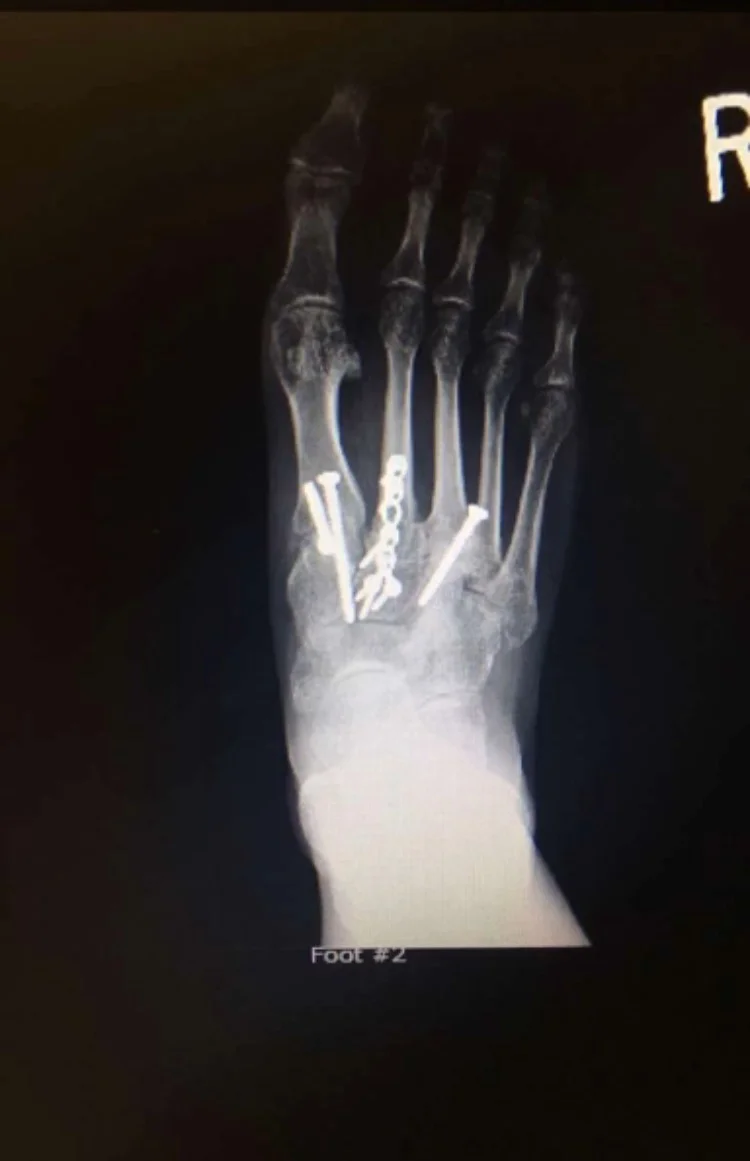

Even though I'm technically recovered, I still have issues. This one injury has thrown my body out of whack, and I'm still trying to regain strength and flexibility in certain areas. I get discouraged during yoga because I can't do poses that I used to have no problems with. I walk with a limp after sitting for long periods. My foot still swells, especially when flying. And have I mentioned those six screws and a metal plate are permanent? Yeah, that's right...they're in there permanently.